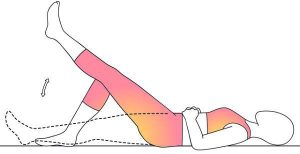

بالا بردن پای صاف

قبل از انجام این حرکت، بهتر است برای ۵ دقیقه با حرکات ایروبیک مانند دوچرخهسواری یا پیادهروی، بدنتان را گرمکنید. بعدازآنکه بدنتان گرم شده، میتوانید به پشت بخوابید و استراحت کنید. یکپا را موازی با کف زمین صاف نگهدارید و زانوی دیگر را خم تنید و کف پایتان را روی سطح زمین قرار دهید. عضلات ران پای صافشده را سفت کنید و سپس آن را حدود سی سانتیمتر از سطح زمین بالا ببرید. این حالت را برای ۵ دقیقه نگهدارید. قسمت بالاتنه و کمرتان باید راحت باشد و همچنین از ایجاد قوس در کمرتان خودداری کنید. میتوانید این حرکت را حداقل دو بار برای هر طرف تکرار کنید. این حرکت روی عضلات روی عضلات چهار سرکار میکند که در جلوی رانها قرار دارند و از مفاصل زانو محافظت میکنند.